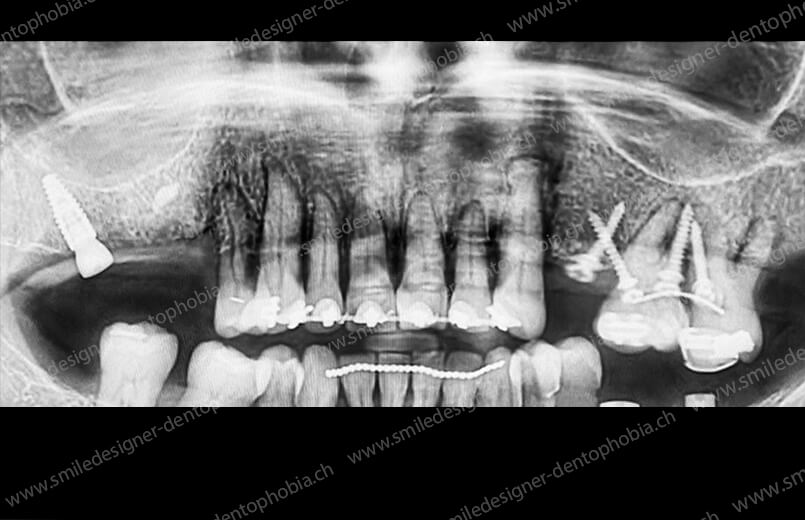

Cas clinique « GOLD STANDARD MCI » maxillaire : Bridge implanto-porté sans extension (ALL ON 10). Version définitive des bridges avec un cosmétique en céramique.